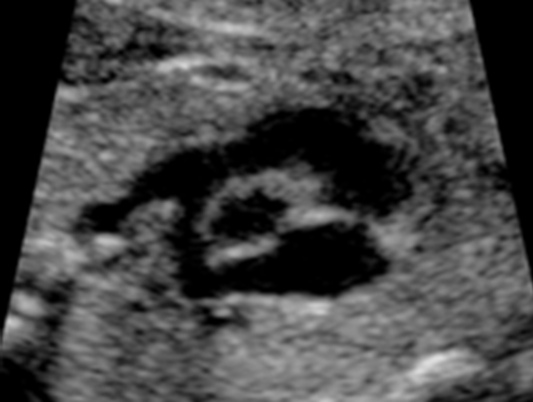

What view is this?

Short-axis Outflow Tract / RVOT